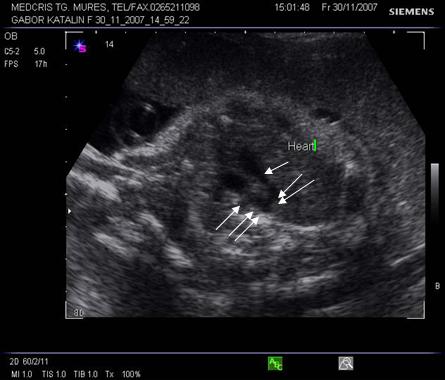

Fig. nr.177. Planul 1 de sectiune, cu imaginea de inima in 4 camere.